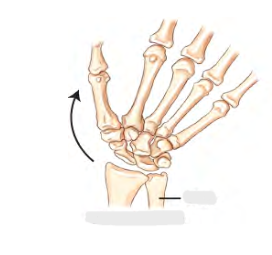

Image 1 : Hyperextension or Dorsiflexion

lifting up hand to the air